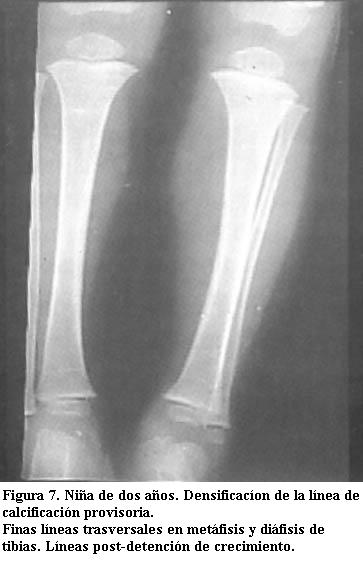

Densificación de la banda de calcificación provisional

Es una banda densa de espesor variable, que se observa con frecuencia en lactantes que tienen problemas nutricionales pasajeros que repercuten en el ritmo normal de crecimiento y formación del tejido óseo. Hay una falla pasajera en la actividad osteoblástica y se acentúa la calcificación provisoria (4).

Es semejante a la osteocondritis de primer grado y se plantea diagnóstico diferencial, pero en general no está afectado el peroné como en el saturnismo (figuras 6 y 7) (12).

Líneas de detención de crecimiento

Son líneas finas, densas, paralelas. Se deben a detención transitoria del crecimiento longitudinal por síndromes febriles, anemia, enfermedad celíaca y otras causas.

Se diferencian fácilmente porque son finas, múltiples y separadas entre sí (figura 7) (4,8).